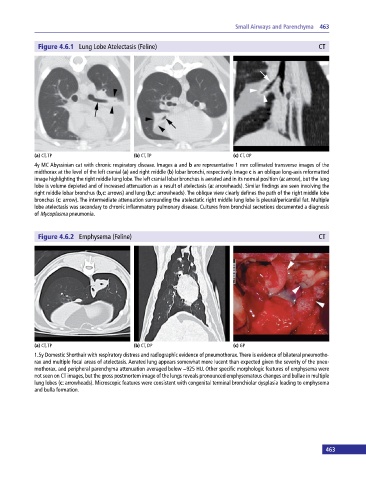

Figure 4.6.1 Lung Lobe Atelectasis (Feline) CT

(a) CT, TP (b) CT, TP (c) CT, OP

4y MC Abyssinian cat with chronic respiratory disease. Images a and b are representative 1 mm collimated transverse images of the

midthorax at the level of the left cranial (a) and right middle (b) lobar bronchi, respectively. Image c is an oblique long‐axis reformatted

image highlighting the right middle lung lobe. The left cranial lobar bronchus is aerated and in its normal position (a: arrow), but the lung

lobe is volume depleted and of increased attenuation as a result of atelectasis (a: arrowheads). Similar findings are seen involving the

right middle lobar bronchus (b,c: arrows) and lung (b,c: arrowheads). The oblique view clearly defines the path of the right middle lobe

bronchus (c: arrow). The intermediate attenuation surrounding the atelectatic right middle lung lobe is pleural/pericardial fat. Multiple

lobe atelectasis was secondary to chronic inflammatory pulmonary disease. Cultures from bronchial secretions documented a diagnosis

of Mycoplasma pneumonia.

Figure 4.6.2 Emphysema (Feline) CT

(a) CT, TP (b) CT, DP (c) GP

1.5y Domestic Shorthair with respiratory distress and radiographic evidence of pneumothorax. There is evidence of bilateral pneumotho-

rax and multiple focal areas of atelectasis. Aerated lung appears somewhat more lucent than expected given the severity of the pneu-

mothorax, and peripheral parenchyma attenuation averaged below −925 HU. Other specific morphologic features of emphysema were

not seen on CT images, but the gross postmortem image of the lungs reveals pronounced emphysematous changes and bullae in multiple

lung lobes (c: arrowheads). Microscopic features were consistent with congenital terminal bronchiolar dysplasia leading to emphysema

and bulla formation.